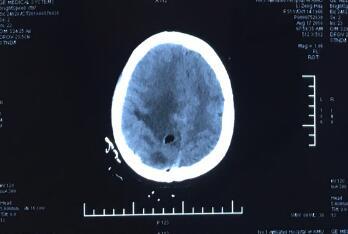

术后复查头颅CT,肿瘤全切除,颅内情况良好

患者,女,51岁,系头痛头晕1月余”入院,入院后完善相关检查,专科检查:神清,精神差,双瞳孔等大等圆,光敏(+),左侧肢体肌力IV级别,右侧肢体肌力正常,余检未见明显异常。头颅MRI检查示:颅内多发性肿瘤,考虑转移瘤可能。遂行PET-CT检查未发现颅外原发性病灶。完善术前常规相关检查,未见明显手术禁忌后,于全麻下圆满完成术中B超引导下一次性切除颅内多发肿瘤手术,在经过家属及护理部的精心护理,患者术后恢复良好。

王斌指出,颅内深部多发肿瘤是神经外科治疗难题,因其位置深、病灶多、解剖关系复杂,常规手术造瘘难以完全探及肿瘤且对脑组织损伤大,容易造成患者功能缺失,致使患者难以接受手术。因此,如何更有效的切除脑肿瘤,并且同时尽量减少脑组织损伤,保留患者功能就成为了神经外科研究的热点与焦点。我院神经外科一病区王斌主任团队在开颅显微切除肿瘤的基础上进一步改良创新开展了术中B超引导下一次性切除颅内多发肿瘤术,成功的为这名患者实施了脑肿瘤完全切除,术后患者功能完全正常。(王斌 洪文明)